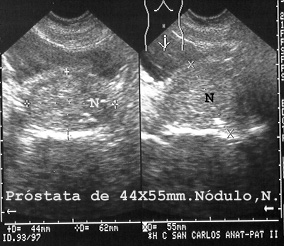

La vejiga llena permite estudiar la próstata y el recto. En la Fig 38 se observa una vejiga en repleción y debajo la próstata muestra un nódulo de hiperplasia.